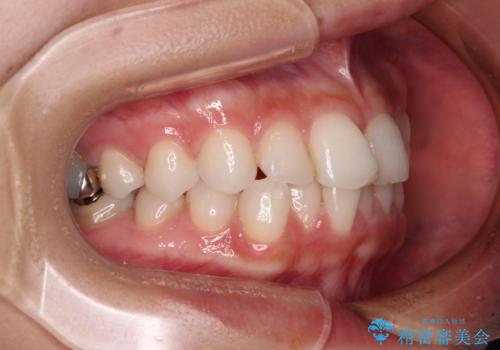

- 歯並びと虫歯をきれいにしたいとのことで来院された患者様です。

楽して短期間で歯列を整えたいとのことで、ワイヤー装置を用いて矯正治療を行い、矯正治療後に下顎の虫歯はセラミックインレー、上顎はPGAインレー(ゴールドインレー)、根管治療を行う歯についてはオールセラミッククラウンにて補綴治療を行うこととしました。

保険治療で用いる樹脂(コンポジットレジン)で行った虫歯治療は、周辺が変色して汚くなっていましたが、下顎はセラミックインレーで審美的に、上顎はPGAインレーで歯に負担の少ない治療を行うことができました。